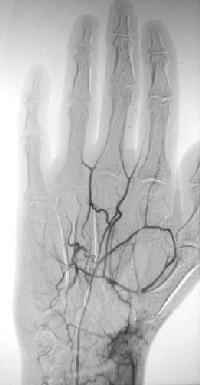

Case 1.

Click for larger image